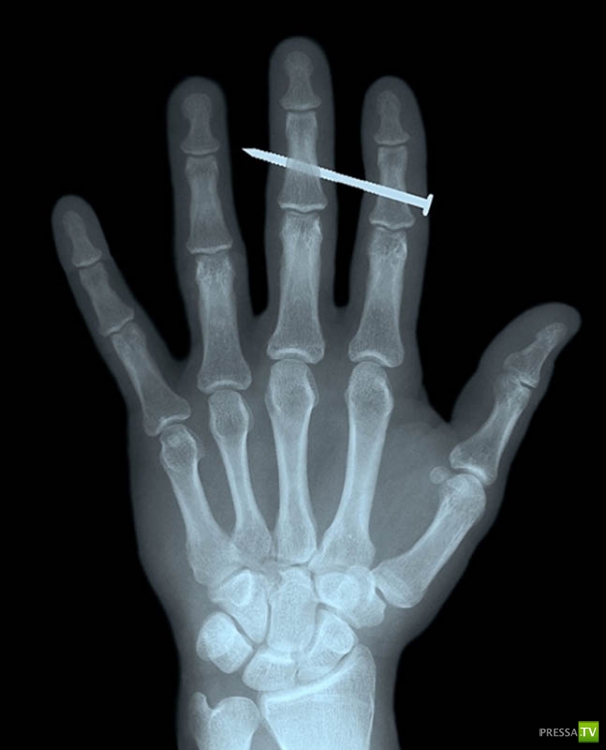

Гвоздь в костях указательного и среднего пальцев взрослого мужчины.